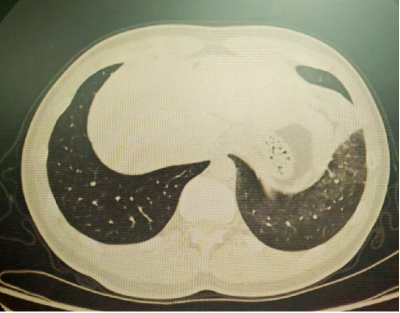

以上是他的胸部CT影像,主要表现为左下肺炎症,片絮影+磨玻璃影。

明确诊断后我们给予了正规治疗,患者咳嗽症状迅速缓解,1月后复查胸部CT提示肺部病变大部分吸收。